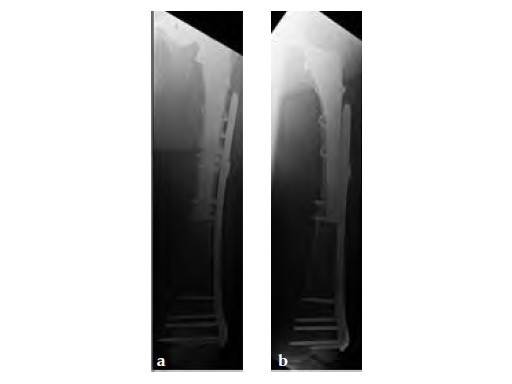

Case provided by Klaus-Dieter Schaser, Berlin, Germany

Case 1: A 78-year-old female sustained a periprosthetic fracture, Vancouver type C, 9 years after a total hip arthroplasty.